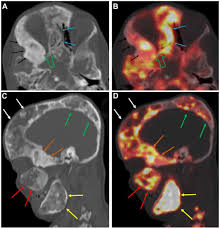

Pet Ct And Pet Mri In Ophthalmic Oncology Review from www.spandidos-publications.com Understanding the nature of cancer. Pet scans also prevent unnecessary surgeries and help suggest which cancer therapies are likely to be most effective for specific tumor types. Because of this high level of chemical activity, cancer cells the combined use of pet scans and ct scans is an effective method for detecting pelvic recurrences of rectal cancer. Pet scans use radioactively tagged molecules (or tracers) to image a wide array of molecular processes and when detected by a pet scanner, the tracers help your doctor to see how well your organs and tissues are working. A pet scan is particularly useful in detecting cancer because most cancers use more glucose than normal tissue uses. In this case, your body position will be very important. Cancer patients and their doctors now have access to a superior imaging technology in pet scans. A pet scan is most often used when other tests, such as mri scan or ct scan, do not provide enough information or physicians are looking for the potential spread of the breast cancer to lymph nodes or beyond.

Those are detected by pet scanner and a computer converts a signal into detailed images showing how organs are working. Pet is speeding the detection of new drug weapons in the war on cancer. The tracer will collect in areas of. Positron emission tomography (pet) imaging or pet scan is a nuclear medicine imaging. Pet scans use radioactively tagged molecules (or tracers) to image a wide array of molecular processes and when detected by a pet scanner, the tracers help your doctor to see how well your organs and tissues are working. Pet scans are a type of test that create 3 dimensional (3d) pictures of the inside of your body. Pet scan is a special type of imaging test in which tracers are injected & are absorbed into organs of body and images are obtained. For cancer and disease detection, the most commonly used nuclear scan is an fdg pet scan. The pet scanner detects signals that are given off from the tracer. Pet/ct, which is a combination of positron emission tomography (pet) with computerized tomography (ct), is a powerful, essential tool for cancer detection and diagnosis. Diagnosis, cancer staging, treatment diagnosed with cancer and are undergoing active treatment, assess treatment response efficiency and perform cancer monitoring with pet/ct scan! A pet scan is not specific for cancer. With that being said, not all cancers can be detected by pet.